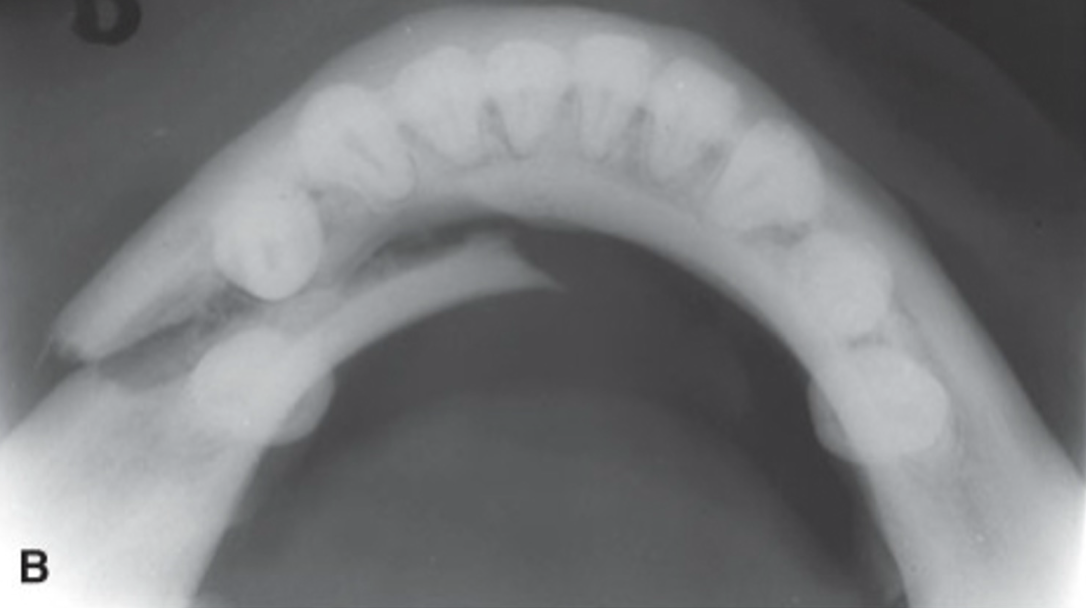

alveolar process fracture

radiolucent line travels through the bone